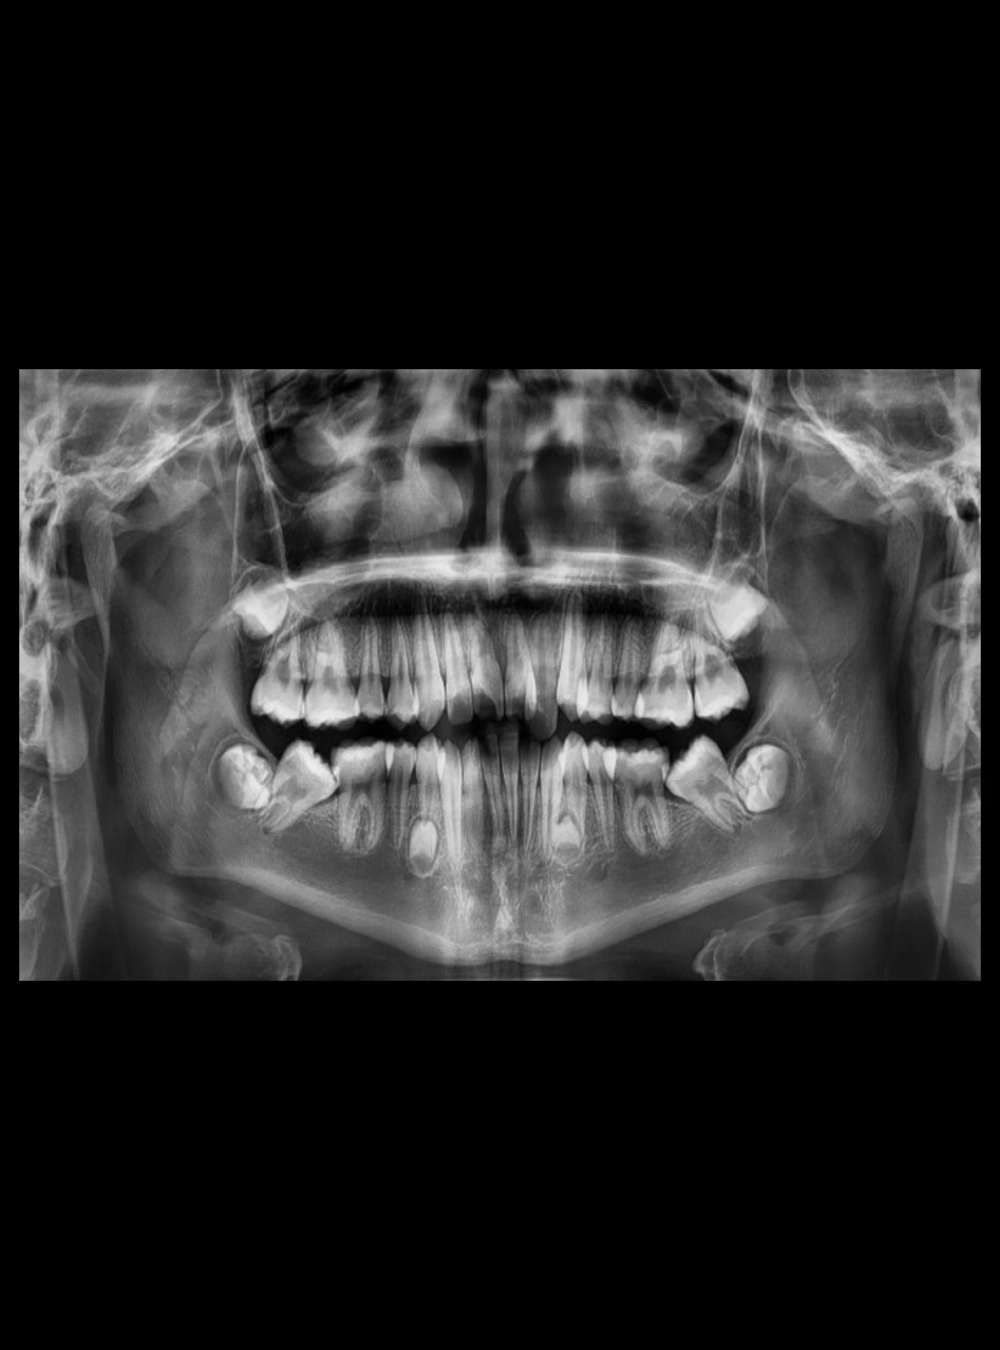

Rx Panorámica

• Panorámica Estándar

Panorámica en Tomografía Cone Beam

Panorámica